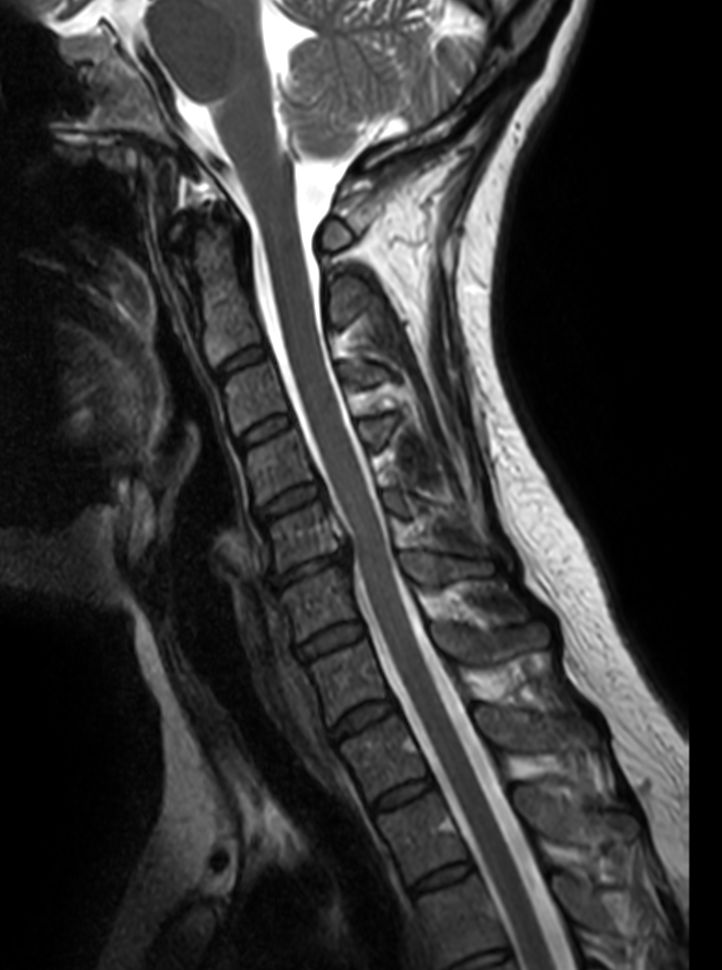

Sagittal T1w TSE

Sagittal STIR TSE